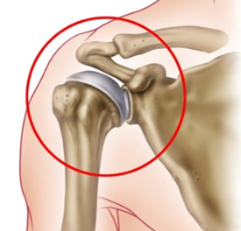

골절, 회전근개 파열, 류마티스 관절염 및 무혈성 괴사 등으로 인하여 어깨관절 연골의 마모 및 손상 등

어깨 관절이 제 기능을 하지 못할 때 관절의 역할을 대신해 줄 수 있는 인공관절로 대체하는 수술입니다.

퇴행성 변화가 현저히 진행되고 통증의 정도가 심할 때

회전근개 파열이 매우 심한 환자에게 관절염이 동반되어 있을 때

보존적 치료에 반응하지 않는 관절염 환자

회전근개 파열 수술 후 재파열되어 다시 수복을 하기 어려운 경우